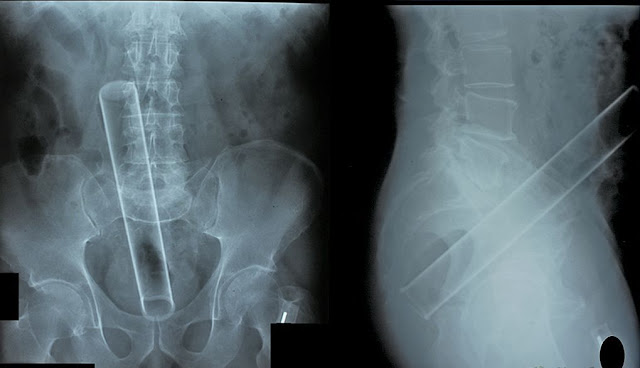

OMG !Para felicidade do ser humano, e da medicina, o Raio-X se faz presente e mostra o quão importante é.Vejamos alguns casos de constrangimento diagnosticados por médicos.